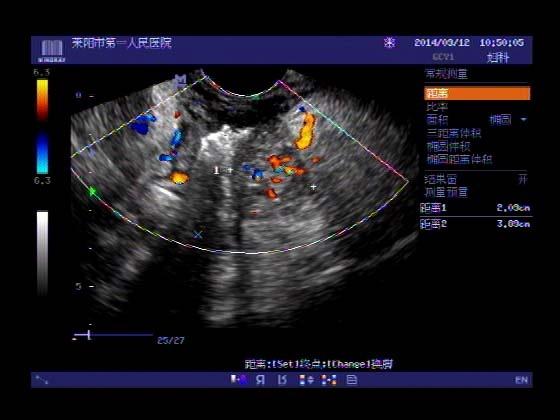

超声入门贴353-----直肠癌伴肝转移

女,66岁